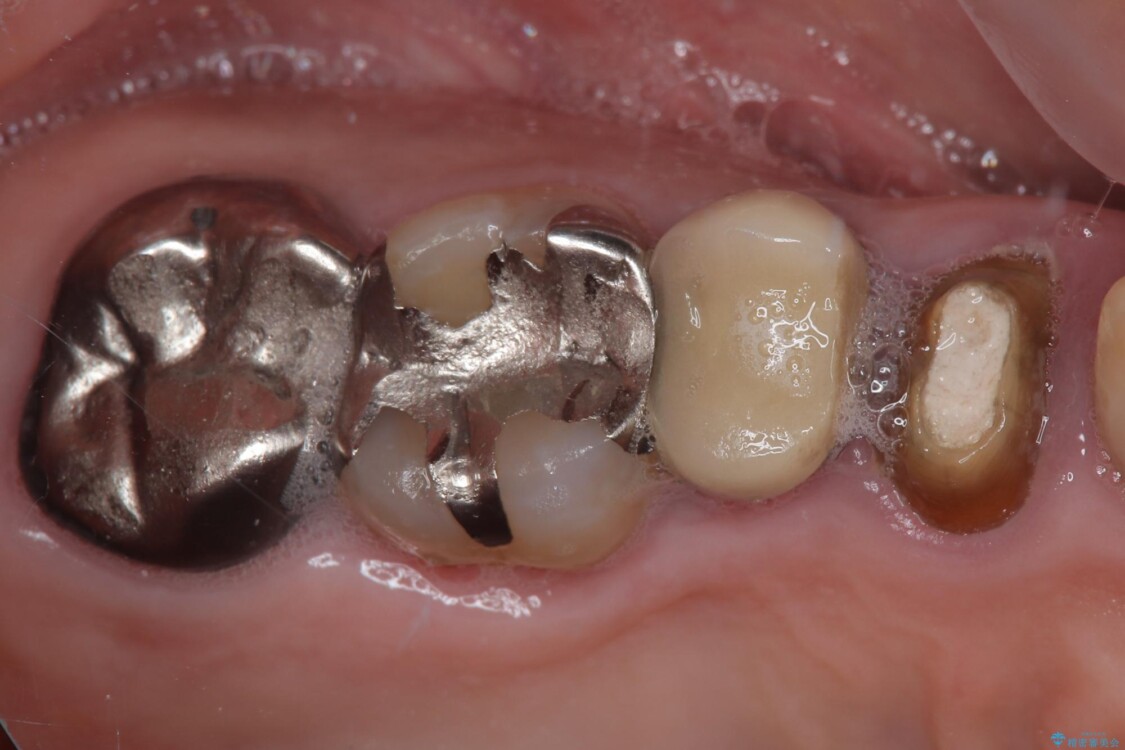

「以前治療した歯の被せものが外れてしまった」とのことで、右上の小臼歯の被せもの脱離を主訴に来院されました。

診察の結果、被せもの(クラウン)だけでなく、土台(コア)ごと外れてしまっている状態でした。根管治療済みの歯ではありますが、今回患者様のご希望により、根管治療の再治療は行わず、補綴処置のみを行う方針となりました。

• 自然な美しさと強度を両立!右上小臼歯の被せもの脱離に対する審美補綴治療 治療前画像